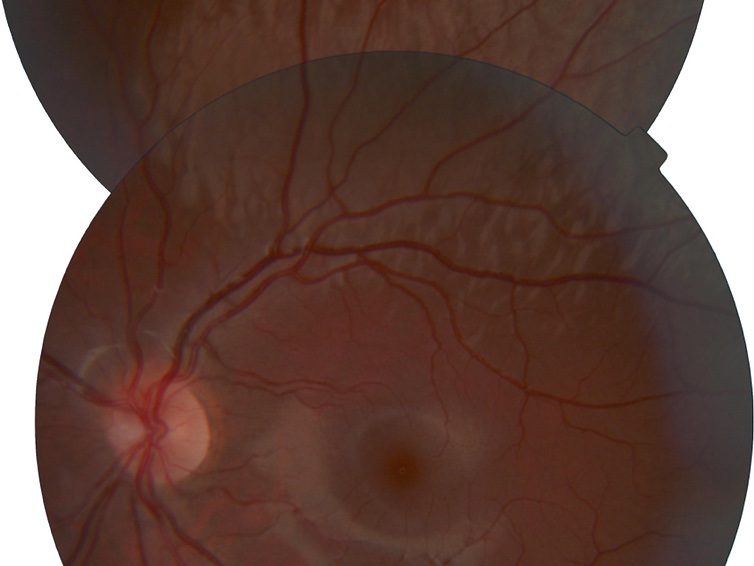

Abstract: Dark without pressure presents as an island or a patch of darker but otherwise normal retina in fundus examination with a condensing lens and a light source. On optical coherence tomography, these lesions show an abrupt attenuation of reflectivity in the ellipsoid zone and the outer segment layer. There have been few case reports since 1975 discussing these findings. To date, little is known about the structural and functional significance of this retinal presentation. Interestingly, these dark without pressure retina have been found in eyes with Oguchi’s disease. The relationship of dark without pressure to Oguchi’s disease remains unknown.